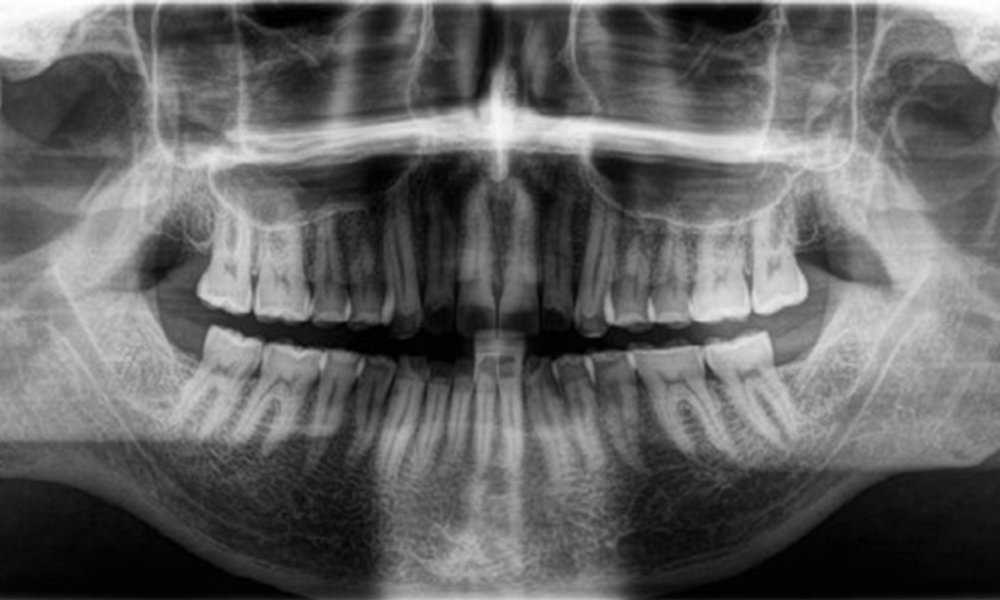

Aspecte radiologice

Se observă o dentiție adultă completă, fără carii sau pierderi osoase vizibile radiologic (Fig. 6). Pierderi cuspidale și de smalț evidente radiologic, cu precădere pe 36 și 37.